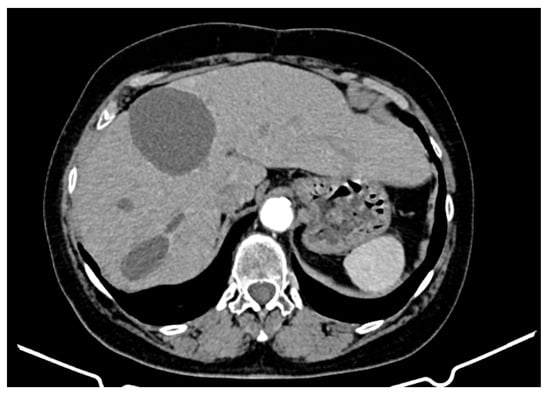

An abdominopelvic CT revealed liver enlargement due to the presence of numerous cystic lesions ranging in size from 1 cm to 18 cm, most of them located in the right hepatic lobe (Figure 1). Two of the largest cystic formations were located at the inferior liver margin, one in segment IVb and the other in segment III of the left hepatic lobe, occupying almost the entire abdominal cavity. The inferior pole of the cystic formation arising from the left hepatic lobe extended into the pelvic cavity (14 × 18 × 18.5 mm AP/Transverse/CC), displacing the transverse colon posteriorly and shifting the jejuno-ileal loops toward the right iliac fossa. The cysts had well-defined contours, but their inner walls varied in thickness and exhibited heterogeneous contrast enhancement. Three hepatic parenchymal calcifications were present in the right hepatic lobe (segments V and VI), with the largest measuring 14 mm and the smallest 2–3 mm; two of them were adjacent to the cystic wall. A thin layer of perihepatic/hepatodiaphragmatic fluid was also noted, with an uneven thickness ranging from 1 to 2.3 cm.

Figure 1.

CT appearance at the time of diagnosis: hepatic tumour formations with a cystic morphology, showing walls of variable thickness and heterogeneous contrast enhancement.